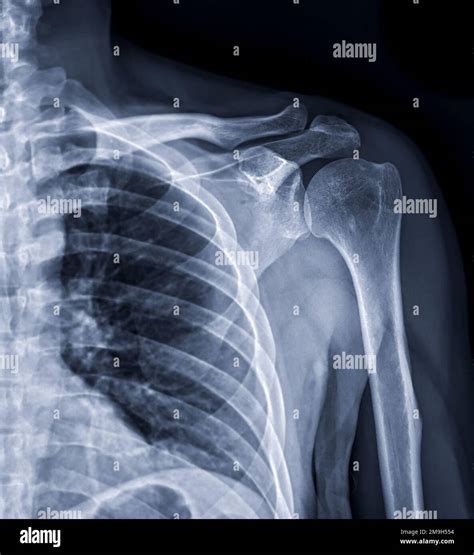

The shoulder joint is a ball-and-socket joint composed of three main bones: the humerus (upper arm bone), the scapula (shoulder blade), and the clavicle (collarbone). The joint is stabilized by a network of muscles, tendons, and ligaments, which allow for a wide range of motion. Understanding the anatomy is essential for interpreting X Ray Shoulder Joint images accurately.

Interpreting X Ray Shoulder Joint Results

Interpreting X Ray Shoulder Joint results requires a trained eye. Radiologists look for specific signs and abnormalities that indicate various conditions. Some key points to consider include:

• Bone Density: Changes in bone density can indicate conditions like osteoporosis or bone tumors.

• Fractures: Visible breaks or cracks in the bones.

• Joint Space: The space between the bones can indicate the presence of arthritis or other degenerative conditions.

• Soft Tissue: Although X-rays primarily show bones, they can also reveal certain soft tissue abnormalities.

Radiologists use these findings to make a diagnosis and recommend appropriate treatment options.